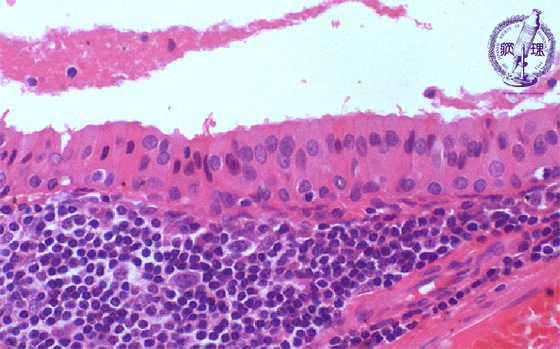

Microscopic finding (HE stain, high-power view):The tumor cells lining the cyst are oncocytic due to cytoplasmic eosinophilic granules. These cells have a dual-layered arrangement with inner tall columnar cells and outer cuboidal cells. The stroma (area below the dotted line) is composed of lymphoid tissue.